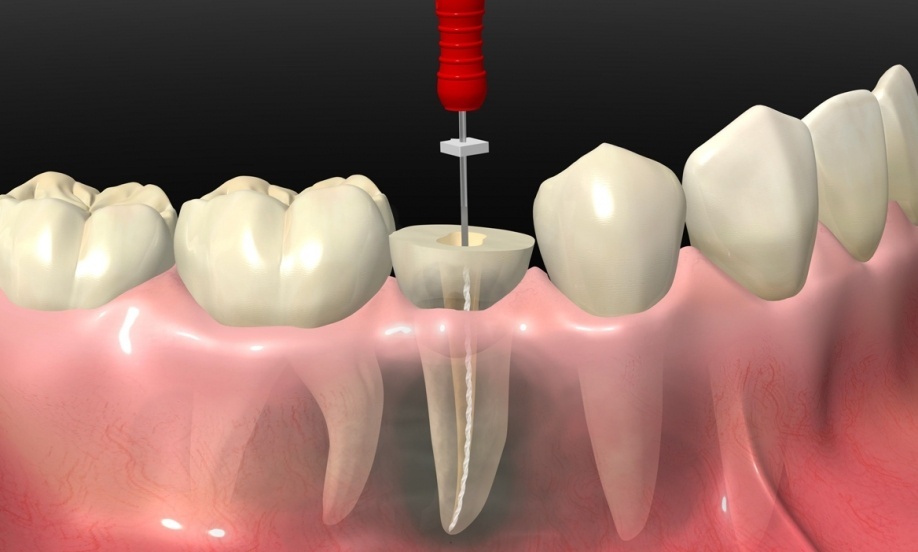

Root Canal Treatment or Tooth Extraction discussions frequently start with a clear understanding of what each procedure entails. Root canal therapy focuses on preserving the natural tooth by removing infected or inflamed pulp, disinfecting the canals, and sealing them with biocompatible materials.

The procedure is often misunderstood as painful or complex, yet modern techniques, including rotary instruments, magnification, and advanced irrigation, have made it highly predictable. Patients retain their natural chewing function, maintain jawbone structure, and avoid the aesthetic and functional challenges associated with missing teeth.

Modern dentistry has revolutionized Root Canal Treatment or Tooth Extraction outcomes through technological innovations. Digital imaging, cone-beam CT scans, and microscope-assisted endodontics enhance precision in canal cleaning and shaping. Ultrasonic instruments and biocompatible sealers improve disinfection and sealing efficacy.

These advancements increase the success rates of root canal therapy and reduce the need for extraction. Patients benefit from minimally invasive procedures, shorter treatment times, and higher predictability, making tooth preservation a more viable and effective option.